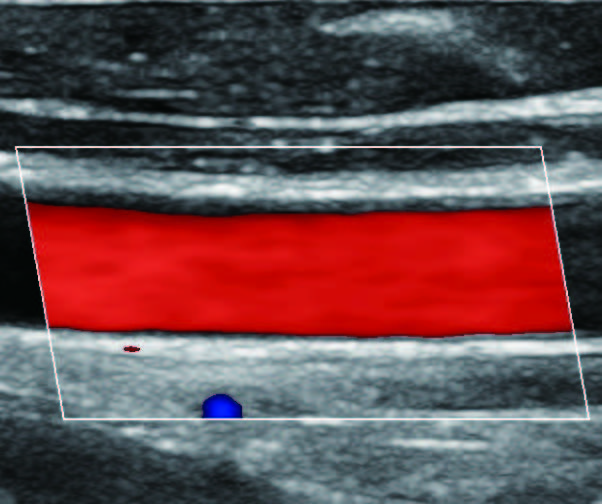

На изображениях, приведенных ниже показаны примеры из клинической практики врачей ультразвуковой диагностики, полученные в процессе апробирования прибора Mindray Resona 7. Приводится наглядные примеры сравнения традиционного режима ЦДК и режима V Flow (Vector Flow).

Изображен ламинарный поток сонной артерии. В режиме ЦДК отсутствует информация о профиле ламинарного потока. Режим V Flow визуализирует не только скоростные характеристики с помощью цветных стрелок, но и предоставляет данные о профиле ламинарного потока (быстрый поток в центре и медленный вблизи стенок сосуда).